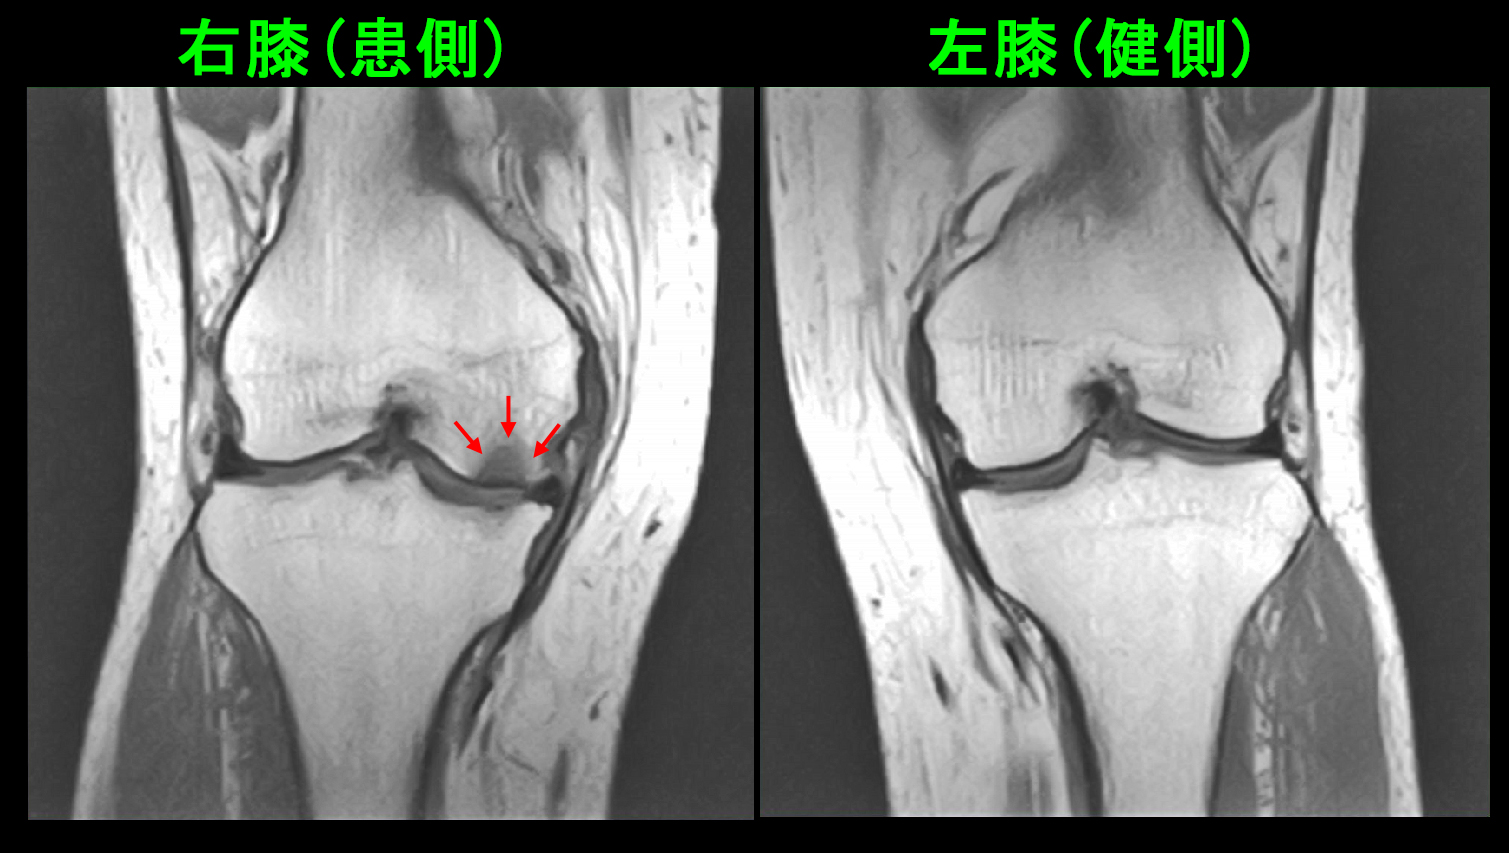

この患者さんは1年半後の平成31年4月27日に反対側の左膝痛で受診され、左大腿骨内顆部に骨壊死を生じていました(赤矢印)。

68才女 MR3.jpg

右側の大腿骨内顆骨壊死は治癒していました(青矢印)。左膝の内顆部の骨壊死は右膝に比較すると小さな領域であったため、2か月半で治癒しています。